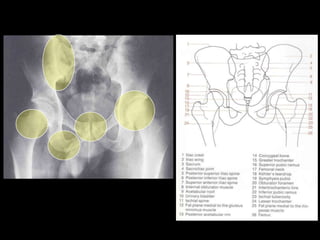

This document provides an overview of normal musculoskeletal imaging. It discusses basic x-ray concepts and densities. It then reviews normal anatomy as seen on x-rays of the skull, spine, pelvis, chest, and extremities. Key anatomical structures are labeled on example x-rays for the shoulder, hip, knee, and foot. Quizzes are included to test recognition of anatomical structures and patient age based on x-rays.